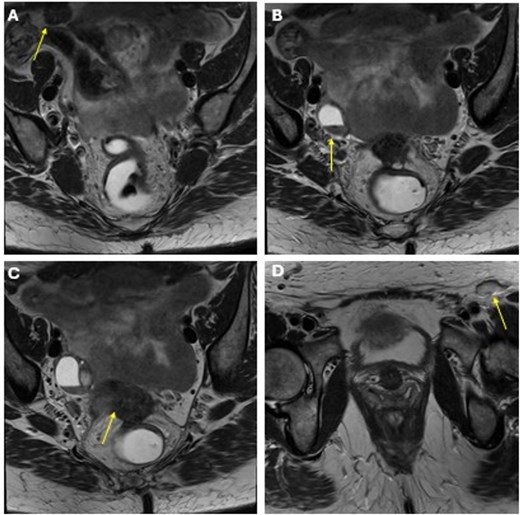

She completed six cycles of adjuvant leucovorin/folinic acid, 5-fluorouracil, and oxaliplatin (FOLFOX) before developing pelvic and perineal discomfort. CT imaging demonstrated suspicious masses of the right abdominal wall (Fig. 1A), right ovary (Fig. 1B), anterior rectum (Fig. 1C), and left inguinal lymph node (Fig. 1D). A fine needle aspiration of the peritoneum and cervix confirmed metastatic colorectal adenocarcinoma. Given the progression despite being on chemotherapy, a multidisciplinary discussion was made to initiate pembrolizumab. The patient completed 1 year of therapy (20 cycles), which she tolerated well. Restaging with esophagogastroduodenoscopy (EGD), colonoscopy, and positron emission tomography (PET) demonstrated stable disease without progression (Fig. 2). MRI imaging redemonstrated essentially stable appearing right rectus abdominus muscle mass measuring 2.1 × 1.6 × 2.2 cm (Fig. 3A), two suspicious ovarian lesions measuring 2.9 × 1.7 × 3.2 and 2.0 × 1.2 × 1.9 cm (Fig. 3B), an additional mass abutting the anterior peritoneal reflection measuring 3.7 × 2.9 × 3.1 cm (Fig. 3C), and prominent 12 mm left inguinal lymph node (Fig. 3D).

MRI obtained status post 20 cycles of adjuvant pembrolizumab with a stable-appearing mass abutting the right rectus abdominis (A), right adnexal masses (B), a mass along the anterior peritoneal reflection abutting the rectum (C), and a left inguinal lymph node (D).